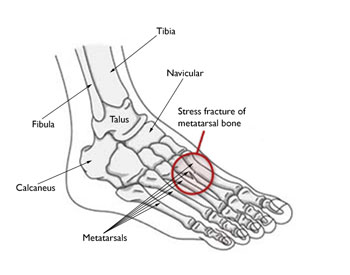

DescriptionStress fractures occur most often in the second and third metatarsals in the foot, which are thinner (and often longer) than the adjacent first metatarsal. This is the area of greatest impact on your foot as you push off when you walk or run.

Stress fractures are also common in the calcaneus (heel); fibula (the outer bone of the lower leg and ankle); talus (a small bone in the ankle joint); and the navicular (a bone on the top of the midfoot).

A00379F01.jpg" title="The most common sites for stress fractures in the foot are the metatarsal bones." credit="">Many stress fractures are overuse injuries. They occur over time when repetitive forces result in microscopic damage to the bone. The repetitive force that causes a stress fracture is not great enough to cause an acute fracture — such as a broken ankle caused by a fall. Overuse stress fractures occur when an athletic movement is repeated so often, weight-bearing bones and supporting muscles do not have enough time to heal between exercise sessions.

The most common sites for stress fractures in the foot are the metatarsal bones.